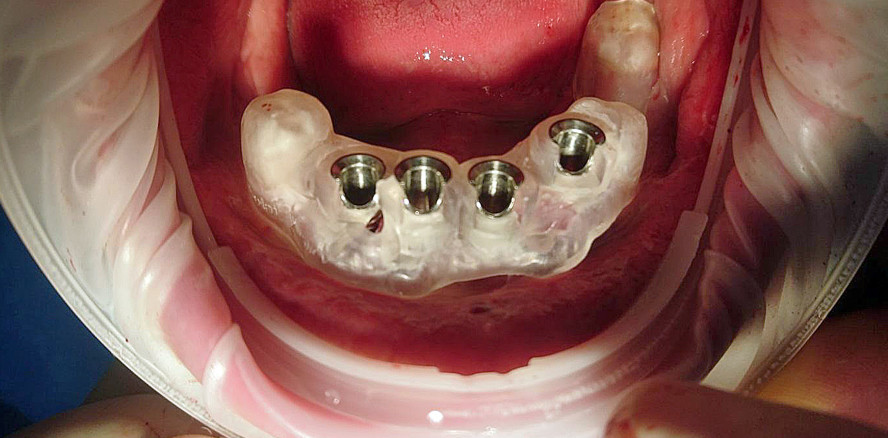

Implantologie 09.11.2018

Sofortversorgung im Unterkiefer mit Stegkonstruktion

Foto: Autorin

Die Operation erfolgte unter Lokalanästhesie, der Patient entschied sich gegen eine Dämmerschlafnarkose. Die Bohrschablone wurde auf den Unterkiefer des Patienten aufgelegt. Nach der Prüfung der Stabilität in der Mundhöhle wurde mit einer Mukoektomie und der Trepanation des kortikalen Knochens sowie der anschließenden Vorbereitung des Implantatbetts begonnen – abhängig vom chirurgischen Protokoll des gewählten Implantatsystems. Bei der Implantation dient die Bohrschablone als intraoperative Kontrolle der Lage und der Achse der Implantate sowie als Kontrolle für die Eindringtiefe der Drehwerkzeuge.

Die Insertion der Implantate erfolgte mit einer leichten subkrestalen Positionierung maschinell (40–45 Nm). Nach Abschluss wurde die nicht mehr erhaltungswürdige Restbezahnung aus dem Unterkiefer entfernt, die zunächst noch zum Halt der Bohrschablone genutzt wurde. Die Prothetik wird direkt auf den Implantaten über die Abutments verschraubt. Die Stegverbindung sorgt für eine sichere Verblockung der Implantate untereinander. Selbst unter Belastung ist nun keine Bewegung der Implantate mehr möglich. Daher gilt die sofortige Versorgung von stegverblockten Implantaten sowohl aus wissenschaftlicher als auch aus erfahrungsgemäßer Sicht als sicher – auch ohne die Osseointegration abzuwarten. Prinzipiell geht es zunächst darum, einen mechanischen Halt zu erzeugen, der im zweiten Schritt einen biologischen und funktionellen Verbund ermöglicht.